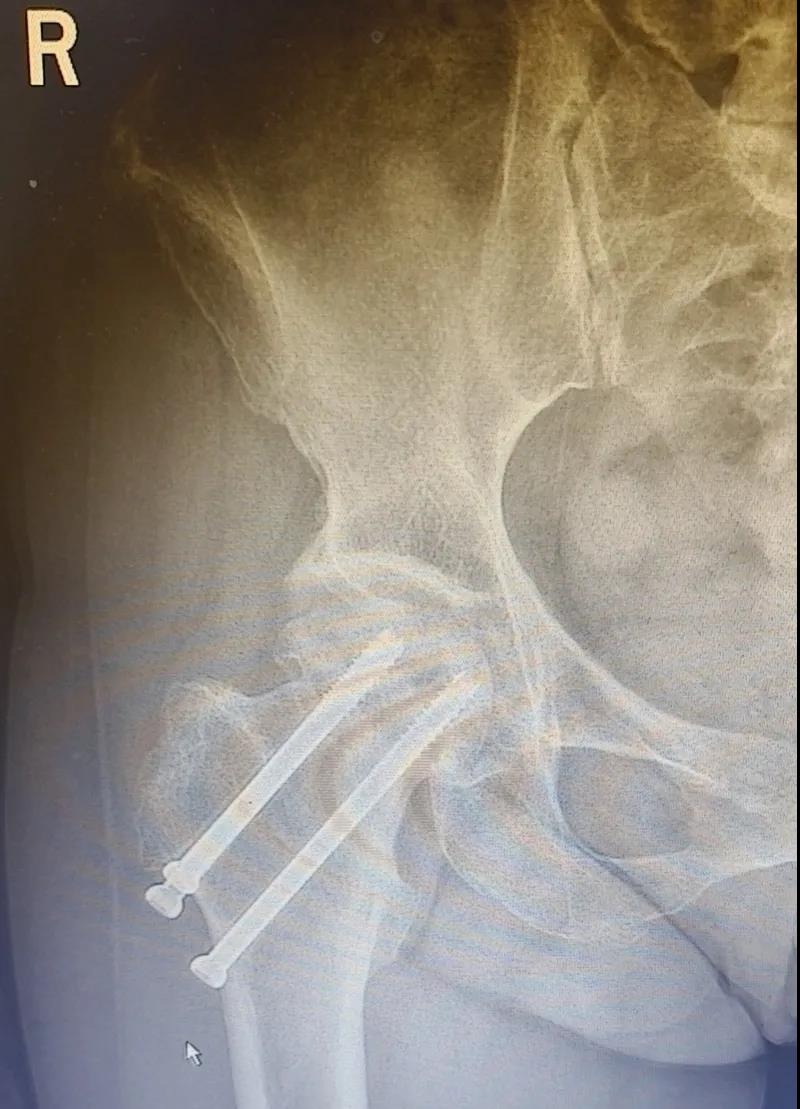

據李女士自述,自己于3年前因外傷致右股骨頸骨折,當時在其他醫院做了右股骨頸骨折閉合復位螺釘內固定術,一年后右髖出現疼痛并逐漸加重,且休息不能緩解,行走時就像有座山壓身上一樣。

結合病癥表現及影像顯示,李女士被診斷為“右股骨頸骨折術后股骨頭壞死”,需要盡快做手術。

(△術前影像,右股骨頸骨折內固定術后股骨頭壞死)